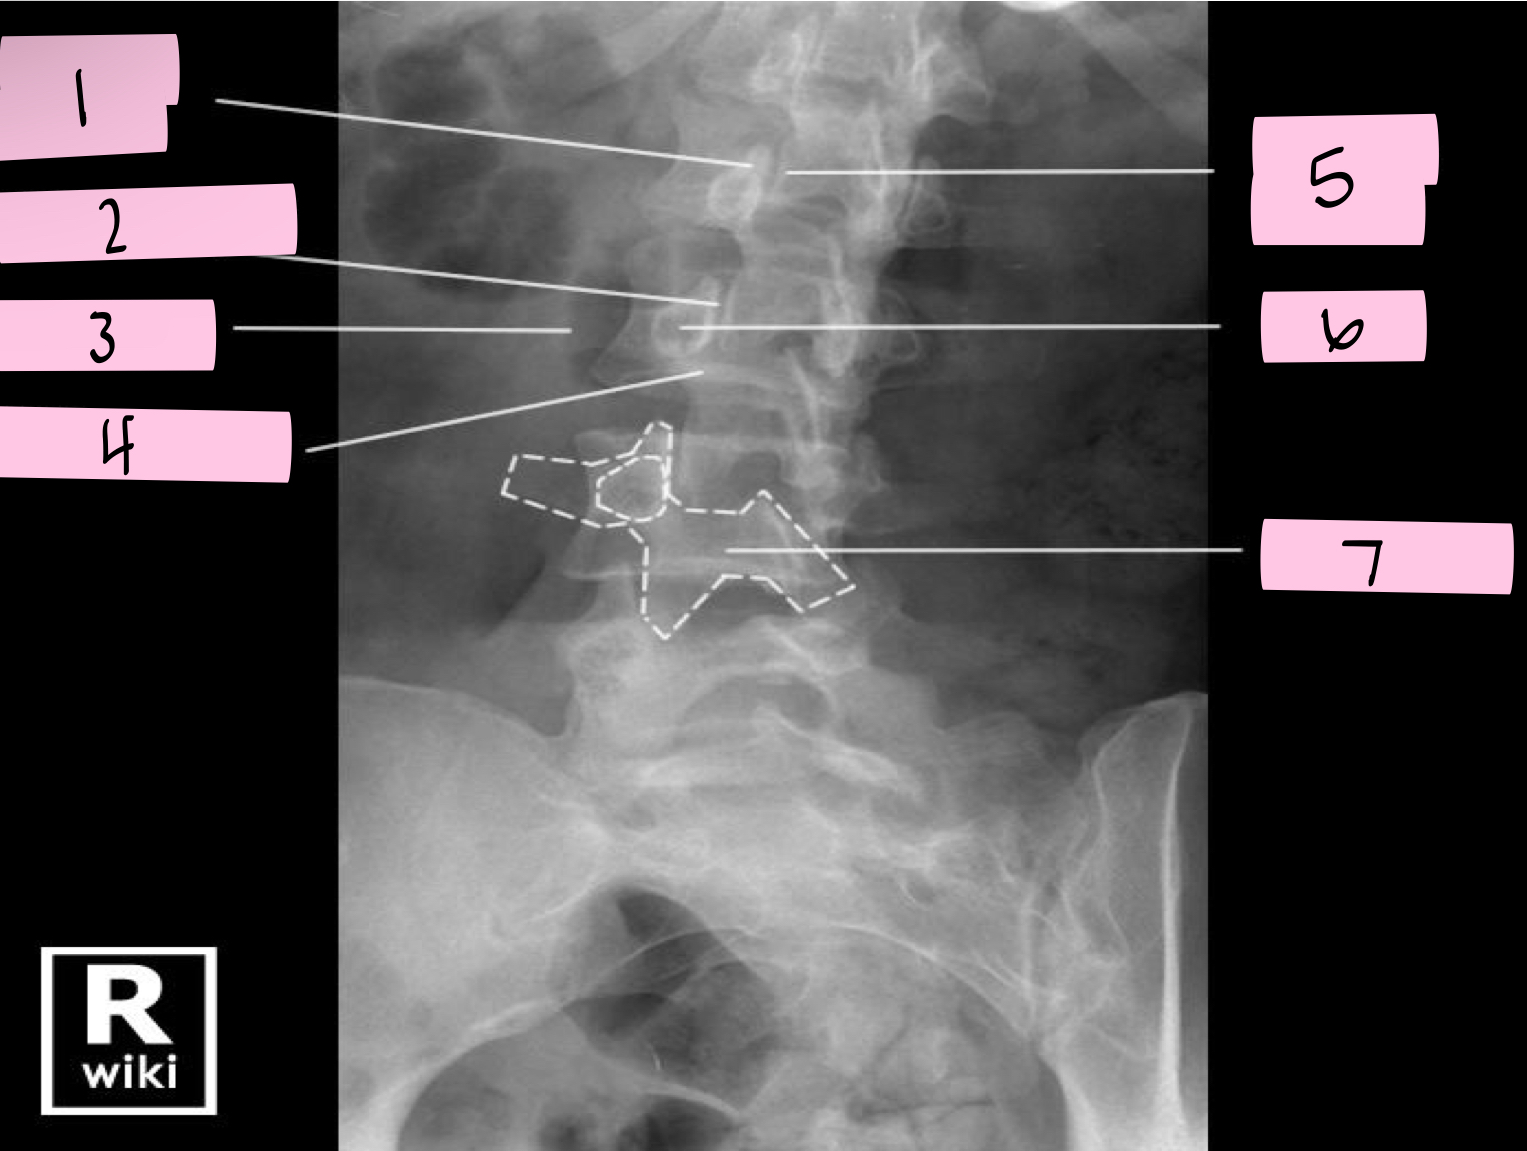

What is 1 pointing to?

Nose- Transverse process

What is 2 pointing to?

Eye- Pedicle

What is 3 pointing to?

Neck- Pars interacticularis (isthmus)

What is 4 pointing to?

Foreleg- Inferior articular process

What is 5 pointing to?

Ear- Superior articular process

What is 6 pointing to?

Tail- Superior articular process of opposite side

What is 7 pointing to?

Body- Lamina and spinous process

What is 8 pointing to?

Hindleg- Inferior articular process of opposite side